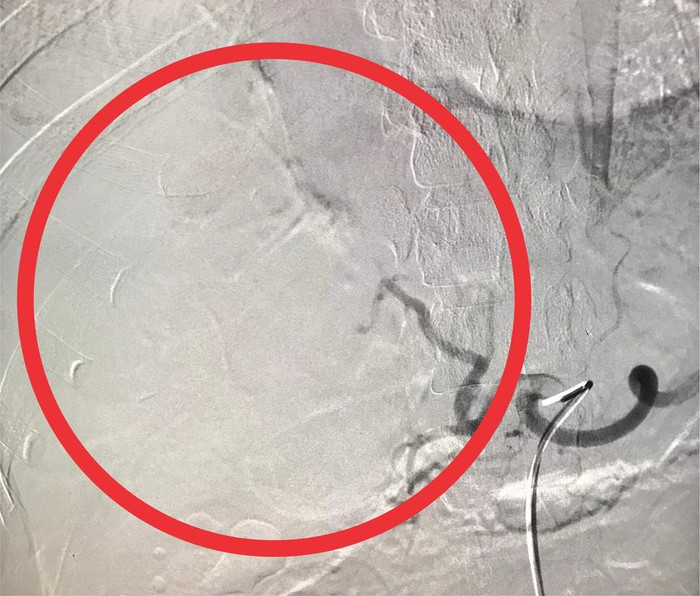

Sau đó, chị L. được chỉ định thực hiện thủ thuật can thiệp chụp và nút mạch cầm máu gan trên hệ thống máy chụp mạch số hóa xóa nền (DSA), kết hợp vật liệu tắc mạch vào động mạch gan phải để tiến hành cầm máu gan vỡ.

Hình ảnh trước và sau khi can thiệp.

Thủ thuật diễn ra trong vòng 40 phút. Sau can thiệp, hiện tại tình trạng bệnh nhân tỉnh, mạch huyết áp ổn định, tiếp xúc tốt, giảm đau bụng. Dự kiến sẽ được xuất viện trong vài ngày tới.